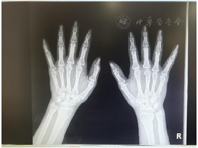

血常规:白细胞5.86×109/L,红细胞沉降率106 mm/h,白细胞介素-6 54.2 pg/ml,铁蛋白652.88 ng/ml,超敏C-反应蛋白120.5mg/l,类风湿因子216.4 U/ml,抗角蛋白抗体+++,抗环瓜氨酸肽抗体>500 U/ml,自身抗体组:ANA 1∶1 000(均质型),ds-DNA(-),可提取的核抗原(ENA)系列阴性,抗中性粒细胞胞浆抗体阳性(+++);过氧化酶抗体阴性;抗中性粒细胞胞浆抗体阴性,蛋白酶PR3抗体阴性,乙型肝炎抗原阴性。肝功能、肾功能正常。X线检查:胸部正侧位,双肺及心膈未见异常。双手腕指关节正位:双手腕指关节构成骨质完整,骨皮质光滑、连续,骨小梁清晰,未见骨质增生、硬化或破坏;关节间隙等宽,关节关系正常(图1)。